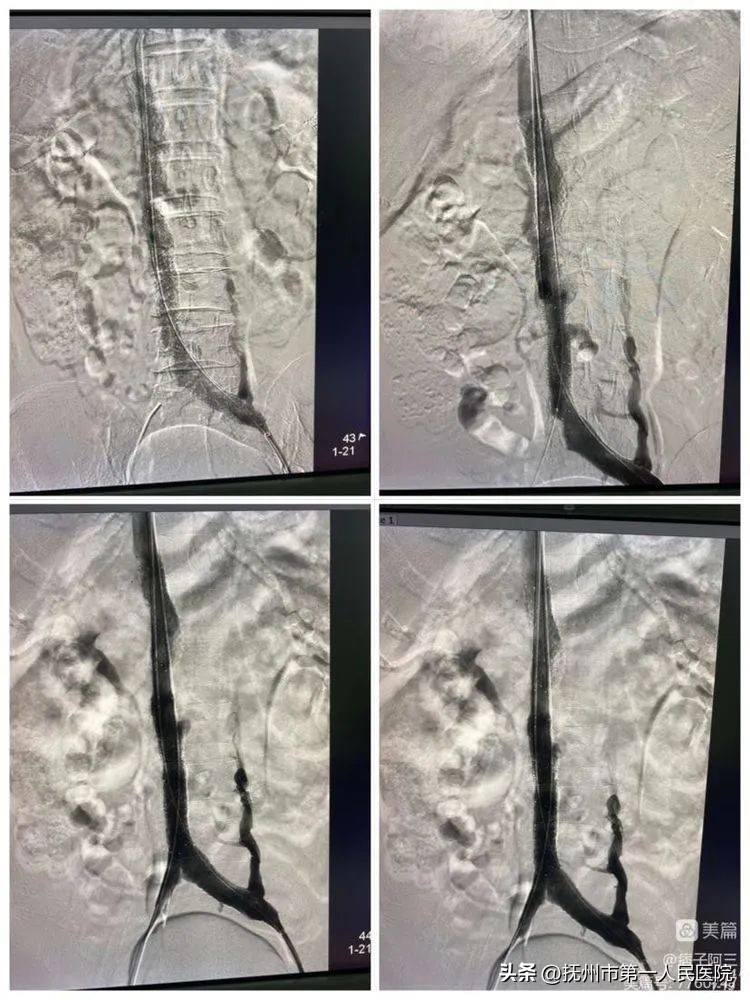

支架植入➕球囊内扩后再次造影及观察10分钟后造影下腔静脉显示均通畅、侧枝明显减少。手术结束